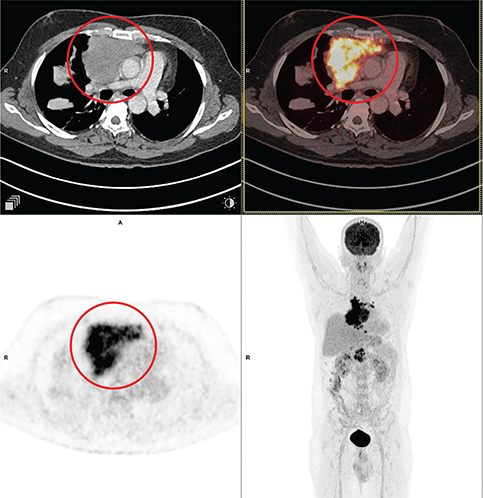

18F-FDG PET/CT in patients with HL and high-grade or aggressive non-Hodgkin lymphoma (NHL) consistently has very high sensitivity (63). 18F-FDG PET/CT improved the characterization of lesions that were uncertain on other types of imaging and often detected nodal and extranodal disease sites that were missed by conventional staging techniques. An example of 18F-FDG PET/CT showing synchronous sites of supra and infradiaphragmatic involvement is seen in Figure 4.

Fig 4

Figure 4. Diffuse large B cell lymphoma. Anterior mediastinal mass that was pathologically confirmed as NHL (Diffuse large B cell lymphoma). FDG PET/CT images include axial CT (top left panel), fused axial PET/CT (top right panel), axial PET (bottom left panel), and maximum intensity projection (MIP) PET image (bottom right panel). In the red circle, an enhancing lobulated intensely FDG avid soft tissue mass is seen in the anterior mediastinum on right side of midline, extending into the middle mediastinum. The lesion shows broad based abutment with the mediastinal pleura and compresses the SVC with resultant luminal narrowing. There was additional FDG avid heterogeneously enhancing lesion in the junction of head and neck of pancreas (not on the included PET/CT images and could be appreciated on the MIP image) that were suggestive of synchronous lymphomatous disease involvement.